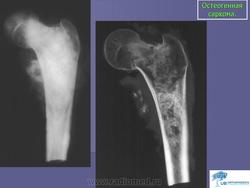

Остеогенная саркома

Рентгенологическая картина остеогенной саркомы отличается большим разнообразием и во многом определяется морфологиче ским вариантом опухоли (остеопластическая, остеолитическая, сме шанная), локализацией и темпами роста. Наиболее характерные рентгенологические признаки проявляются при разрушении коркового слоя кости и при прорастании опухоли в мягкие ткани, т. е. уже в позднем периоде развития заболевания. При этом своеобразные из менения возникают в отслаивающемся периосте с образованием на границе дефекта коркового слоя и пораженных опухолью мягких тканей характерного «козырька» или «треугольной шпоры», распо ложенной под углом к длинной оси кости. Определенное диагно стическое значение имеет обнаружение так называемых «спикул» - реактивных костных разрастании, образующихся в мягких тканях при прорастании в них опухоли. «Спикулы» на рентгенограммах об разуют характерный радиакальный рисунок, располагаясь перпен дикулярно к длинной оси кости.

Остеоидная саркома. По частоте занимает первое место среди всех злокачественных новообразований костей, составляя, по данным разных авторов, от 30 до 80% первичных сарком скелета. Встречается преимущественно у лиц детского, юношеского и молодого возраста (10-30 лет). Несколько чаще болеют лица мужского пола. Поражает главным образом метафизы длинных трубчатых костей, составляющих коленный сустав (примерно половина наблюдений), а также плечевой кости. На первом месте стоит поражение бедренной, затем большеберцовой и плечевой костей. Реже опухоль локализуется в лопатке, костях таза, черепа и др. Главный симптом заболевания - боли, которые становятся постоянными, прогрессируют в своей интенсивности и оказываются мучительными. По мере развития процесса возникают и другие клинические признаки - припухлость, опухоль различной величины, расширение кожных вен, повышение местной температуры. Появляются хромота, иногда легкая контрактура в суставе. В некоторых случаях могут возникать патологические переломы. Для остеогенных сарком весьма характерно раннее метастазирование в легкие; метастазы в лимфатических узлах наблюдаются лишь в единичных случаях.

Рентгенологически различают три формы остеогенных сарком: остеолитическую, остеопластическую (склеротическую) и смешанную. Остеолитическая форма характеризуется появлением в кости очага деструкции различных размеров с нечеткими неровными контурами, который располагается обычно эксцентрически. На первых этапах заболевания периостальная реакция почти не выражена. В дальнейшем происходит разрушение коркового слоя, отчетливо выявляется периостальная реакция с образованием характерного периостального козырька. При остеопластической форме в очаге поражения кость неравномерно уплотнена, веретенообразно утолщена. По мере роста опухоли надкостница отслаивается и возникает периостальный козырек. Образуются игольчатые, пластинчатые, гребневидные или веерообразные периостальные разрастания (спикулы). Рост опухоли и разрушение костного вещества происходят в одинаковой степени как по длиннику, так и по поперечнику кости. Костно-мозговой канал довольно быстро выполняется опухолью, на фоне которой могут прослеживаться участки обызвествления.

Остеогенная саркома.